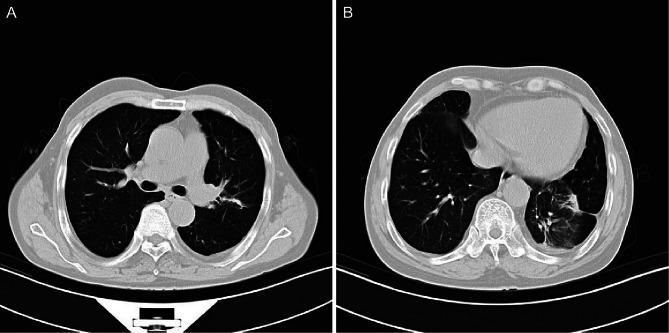

A 66-year-old man presented with cough, sputum, chest tightness and weight loss persisting for 1 month. Chest X-ray revealed a space-occupying lesion in the left lung. Further CT imaging demonstrated irregular soft tissue masses in both the upper and lower lobes of the left lung. Although the imaging findings suggested lung cancer, the final pathological diagnosis confirmed AFOP. The patient was treated with methylprednisolone, resulting in substantial improvement of the upper lobe lesion, whereas the lower lobe lesion showed minimal response. Following the addition of mycophenolate mofetil, the lower lobe lesion decreased substantially. Multiple lung biopsies confirmed the diagnosis of AFOP, with no evidence of a malignant tumour.

一名66岁男性,出现咳嗽、咳痰、胸闷和体重减轻症状持续1个月。胸部X线显示左肺有占位性病变。进一步的CT成像显示左肺上叶和下叶均有不规则软组织肿块。尽管影像学表现提示肺癌,但最终病理诊断确诊为AFOP。患者接受甲泼尼龙治疗后,上叶病变有显著改善,而下叶病变反应极小。加用霉酚酸酯后,下叶病变明显缩小。多次肺活检确诊为AFOP,无恶性肿瘤证据。